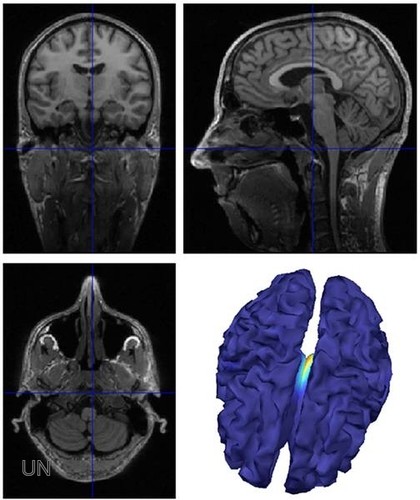

Nuevo método no invasivo para detectar epilepsia.